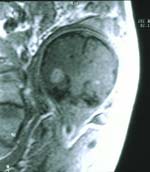

Aide de l’IRM qui donnera l’extension qui détermine le pronostic

L’IRM précise l’extension au niveau des organes de voisinage

IRM :